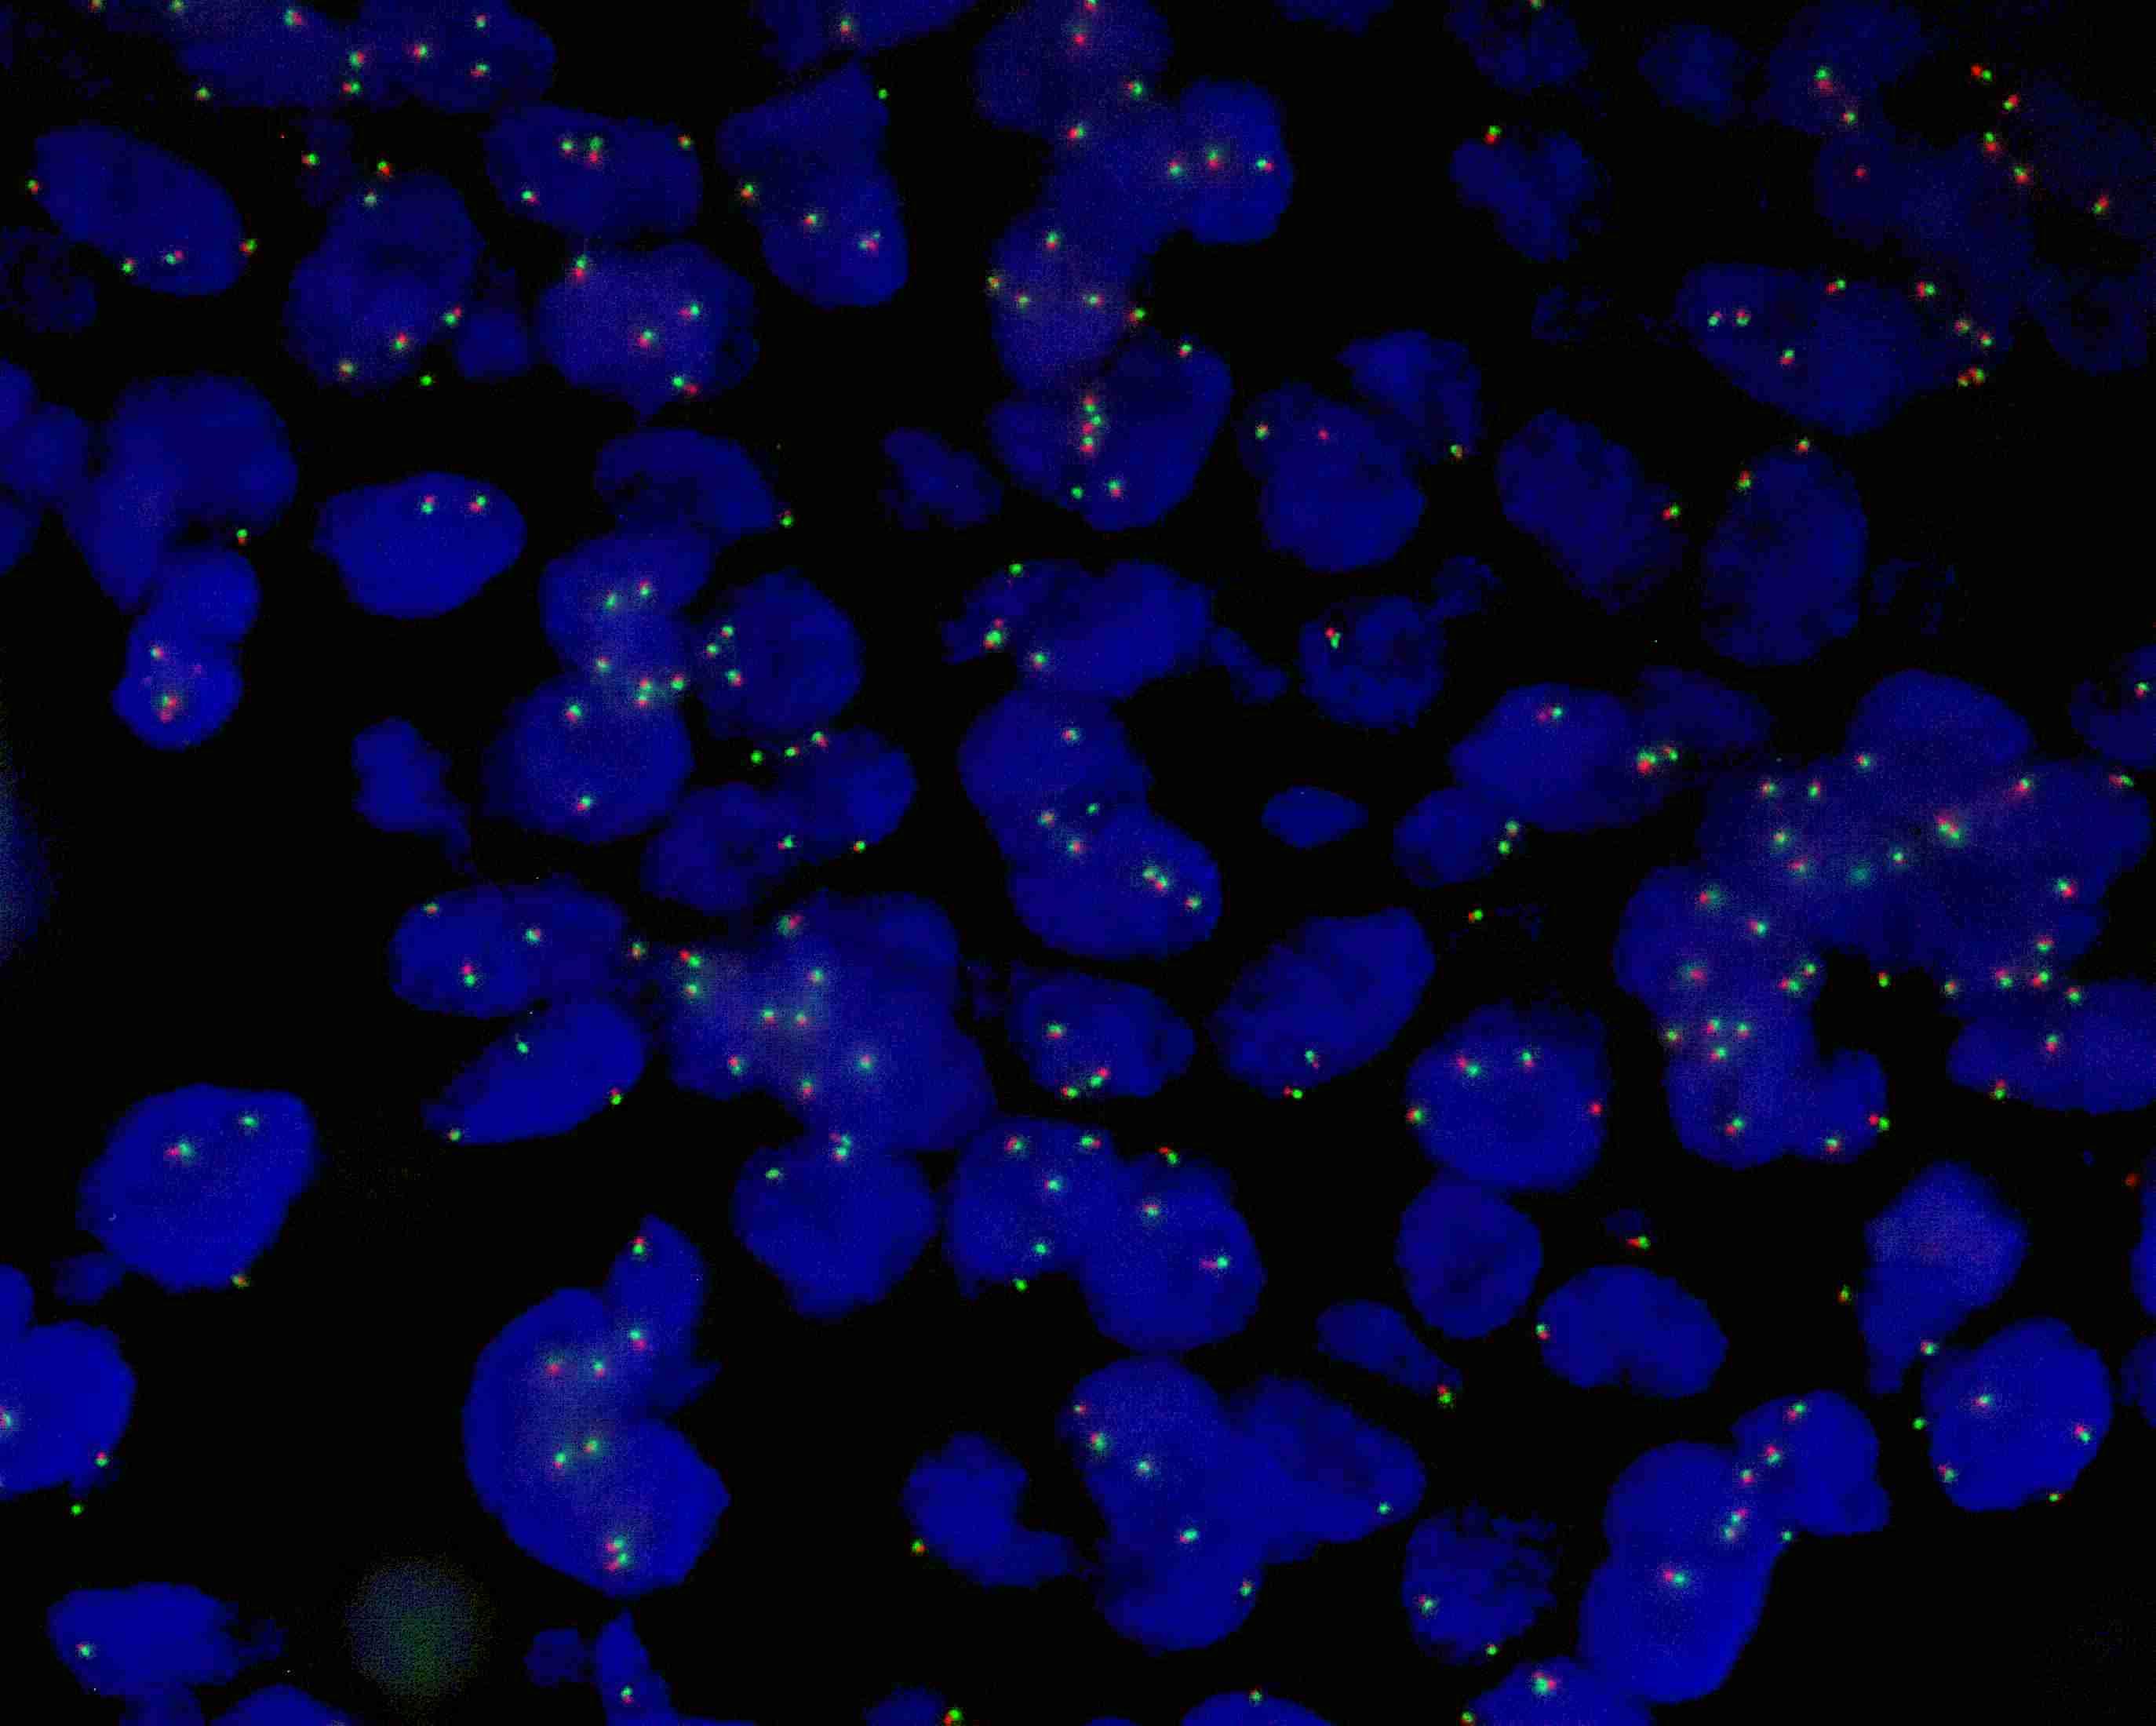

MAML2 (11q21) gene break apart probe reagent

MAML2 dual color probe

MAML2 gene 3’ end labeled as orange, with a length of 330 kb; MAML2 gene 5’ end labeled as green, with a length of 800 kb.